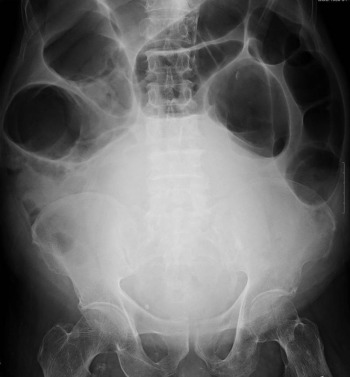

Sagittal reformatted contrast enhanced abdominal computed tomography (Fig. 2 ) showed the Chilaiditi’s sign (small arrow) and enlarged prostate gland, causing urine retention and exaggerative vesical distension (large arrow). A Foley catheter was inserted and 1850 mL clear urine was drained out. The clinical symptoms improved. Because this patient had severe congestive heart failure, he underwent long-term Foley catheter insertion instead of transurethral prostatectomy. Hepato-diaphragmatic interposition of the bowel, known as Chilaiditi’s sign, is a rare and an often asymptomatic anomaly. When this discovery is accompanied by gastrointestinal symptoms, such as constipation, abdominal pain, distension, and vomiting, it is known as Chilaiditi syndrome.

Figure 2.

Sagittal reformatted contrast enhanced abdominal computed tomography shows the Chilaiditi’s sign (small arrow) and enlarged prostate gland, causing urine retention and exaggerative vesical distension (large arrow).